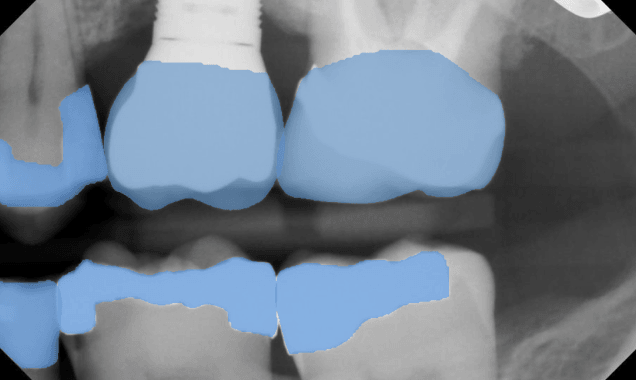

Restorations

7/7Overjet highlights past restorative treatments, like implants, crowns, and fillings.